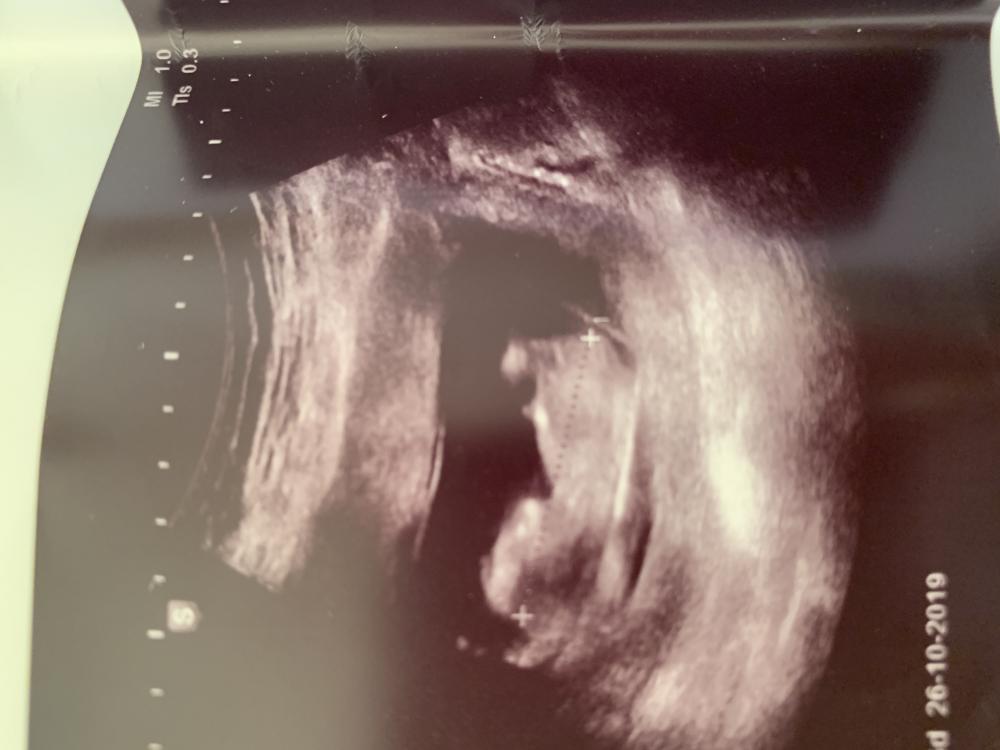

image.jpg من خبيره بنظرية الناب

ارسلت صورة سونار والي فاهمه بنظرية الناب تقولي ايش جني الجنين

ارسلت صورة سونار والي فاهمه بنظرية الناب تقولي ايش جنس الجنين